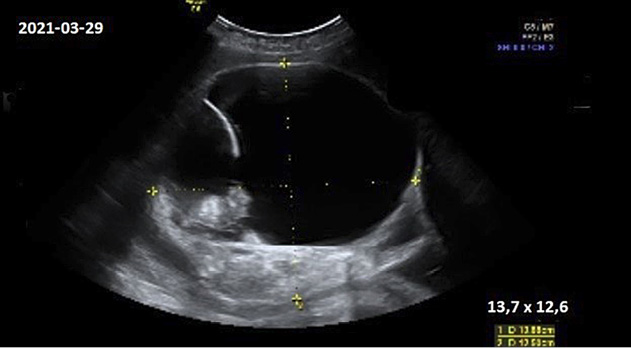

Moteris pakartotinai konsultuota 30, 34 ir 36 nėštumo savaitėmis VUL SK Perinatologijos koordinavimo centre. Stebėtas teratomos augimas: atitinkamai 9,2×7,3 cm, 11,9×12,9 cm ir 13,7×12,6 cm; struktūros pakitimų nenustatyta (darinys mišrios struktūros, turi pertvarą ir intrapozityvių intarpų, kurie sudaro 1/3 naviko tūrio) (ultragarsinis vaizdas pateiktas 1 pav.). Kitų vaisiaus patologijų nepastebėta. MRT tyrimas neindikuotinas.

1 pav. Ultragarsinis teratomos vaizdas 36 nėštumo savaitę (13,7×12,6 cm dydžio heterogeninės struktūros darinys su intrapozityviais intarpais uodegikaulio srityje)